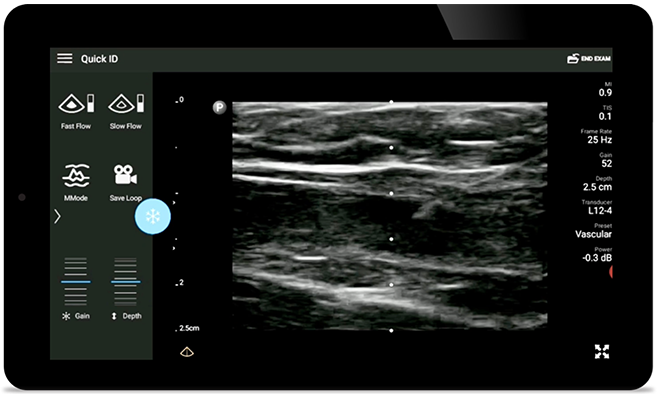

• 12 to 4 MHz extended operating frequency range • Aperture size: 34mm • 2D, steerable color Doppler, M-mode, advanced XRES and multivariate harmonic imaging, SonoCT • High resolution imaging for shallow applications: soft tissue, vascular, superficial, musculoskeletal, and lung • Center line marker • USB-C transducer with replaceable cable